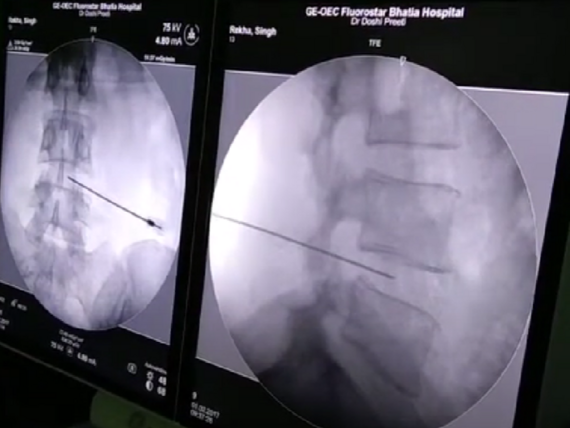

Pod lokální anestezií a s pomocí zobrazovacích metod lékař zavede tenkou jehlu do postižené ploténky. Skrz ni je následně zavedeno laserové vlákno, které odpaří malé množství ploténkové tkáně. Tím se sníží tlak uvnitř ploténky a uvolní se tlak na nervy, což vede k úlevě od bolesti.